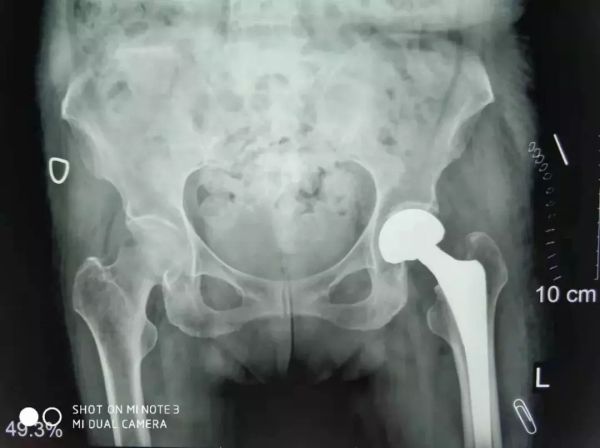

患者卧床两个月后骨折移位更大了

关节科罗军主任和易观俊主治医师联合麻醉科、内科、超声科专家集体会诊及评估,并确定了最佳手术方式和麻醉方案,并积极做好充分的术前准备。于是,11月2日在危立军副院长带领手术团队按照术前的讨论方案,在腰部麻醉下行人工股骨头置换,手术仅用了20分钟。

患者股骨头置换手术照片